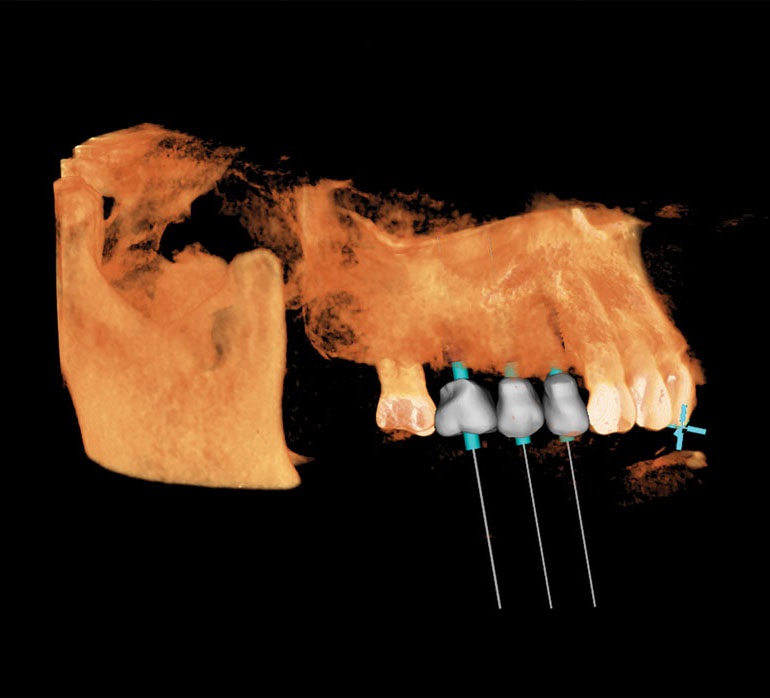

Recently, I placed three implants in Teeth 3, 4 and 5 in conjunction with a sinus lift. Implants in such close proximity to one another can be a challenge even for a specialist. By using the preplanning software, I virtually placed the implants precisely where I wanted them to go, as shown in Figs. 7, 8 and 9. I was thrilled with the outcome. As you can see on the X-ray in Fig. 10, the implants were placed precisely according to the plan.

Fig. 8: 3D plan shows rendering with bone hidden, to make implant

placement visible.